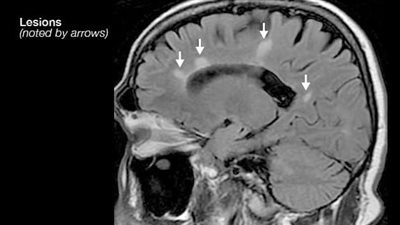

البزل الشوكى والرنين المغناطيسي يسهمان في تشخيص التصلب المتعدد

23/May/2023